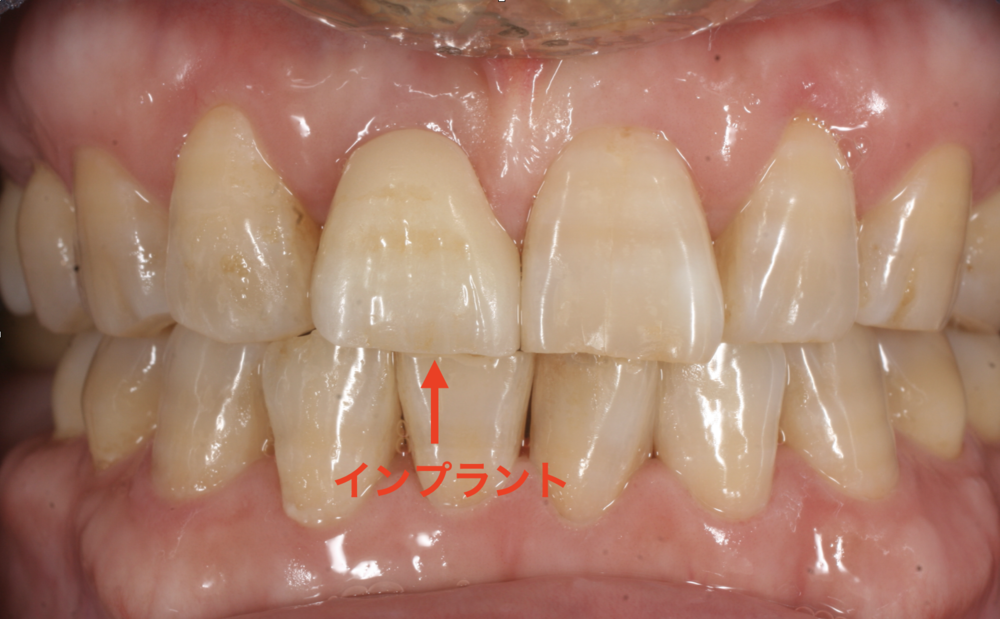

治療後は仮歯を経て、最終的に自然な色調のセラミッククラウンを装着し、

周囲の歯と調和した仕上がりになりました。

曽我歯科医院三軒茶屋では、このような前歯のインプラント治療も行っております。見た目の自然さや審美性が求められる前歯部では、骨や歯ぐきの形態を保ちながら治療を進めることが大切です。